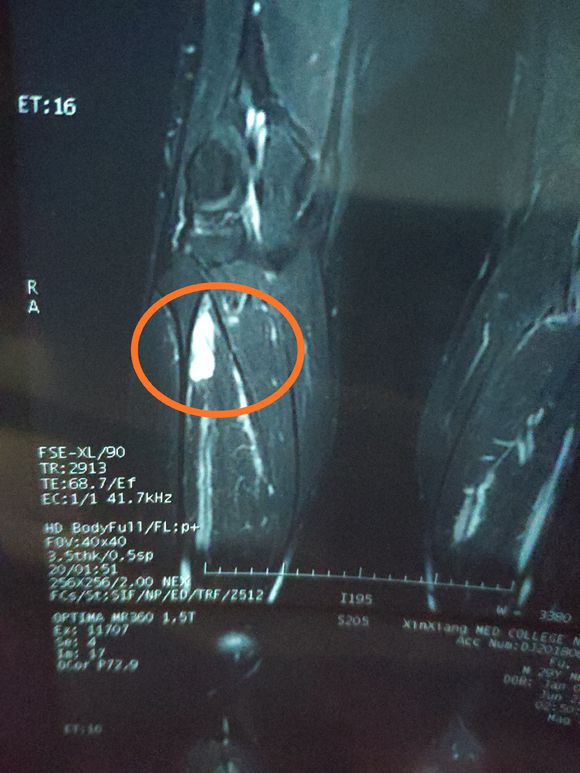

说说第一次化疗对我来说真的太难了~第一次化疗化疗结束后,用了三种药联合化疗,计量很大,止吐药吃的是大麻做的回家是没怎么吐...